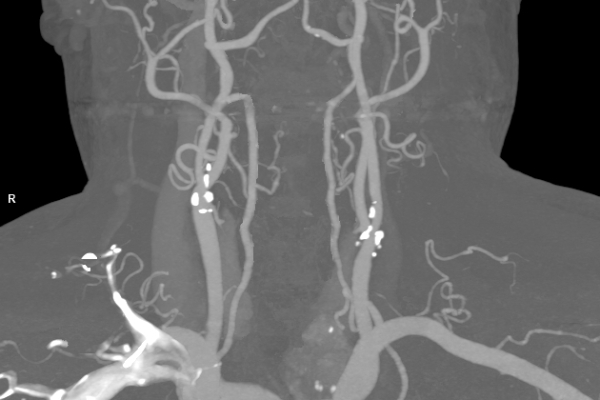

• Gefäßdiagnostik (CT-Angiographie)

Wir bieten ein breites Spektrum an Untersuchungen an, von Standarduntersuchungen der Gelenke, Organe oder großflächigen Körperregionen bis zu Spezialuntersuchungen zum Beispiel des Herzen oder der Gefäße. Zusätzlich werden Angiographien (Darstellung von Blutgefäßen), Endometriose-Abklärungen und Mamma-Untersuchungen durchgeführt. Genauere Details können Sie der MRT/CT-Übersicht und der Preisliste entnehmen, oder Sie wenden sich direkt an unser Team, das Sie gerne zur passenden Untersuchung berät.

Ja, unsere Radiologie bietet auch Sonographie- (Ultraschall-)Untersuchungen an. Untersucht werden unter anderem Abdomen, Becken, Leiste, Brust, Venen und Gefäßen.